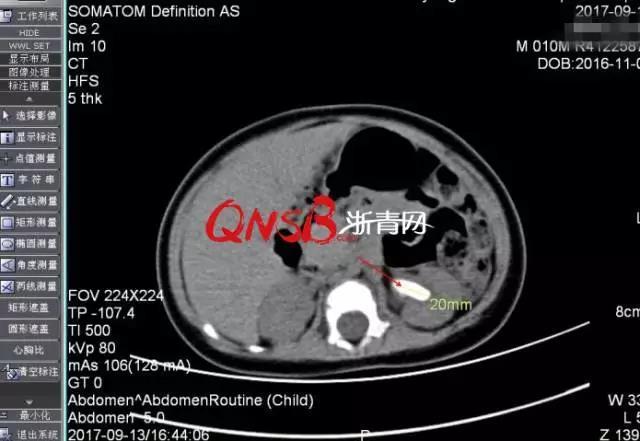

| Kết quả chụp CT sỏi thận của Tiểu Ái. |

Bác sĩ cho biết bé đã mắc phải chứng sỏi thận. Điều khiến nhiều người ngạc nhiên là trong thận trái của bé trai 10 tháng tuổi có một viên sỏi đường kính 2 cm và đường niệu quản bị giãn.